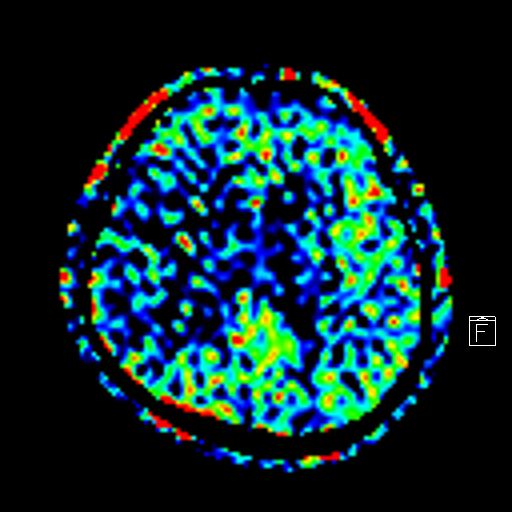

- 脳血管の異常(脳動脈瘤、血管の狭窄など):

脳動脈瘤は破裂するとくも膜下出血を引き起こす危険な病気です。MRIのMRA(MRアンギオグラフィー)という手法を用いることで、脳の血管を立体的に描出し、動脈瘤や血管の狭窄などを早期に発見することが可能です。 - 脳梗塞・脳出血の有無、隠れ脳梗塞の発見:

過去の小さな脳梗塞や出血の痕跡、自覚症状のない隠れ脳梗塞などもMRIで検出できます。これらは将来的な脳卒中のリスクを示す重要な情報です。 - 脳腫瘍の有無: